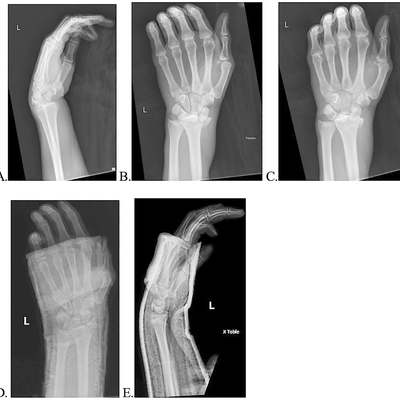

Click on an image below to view more info.